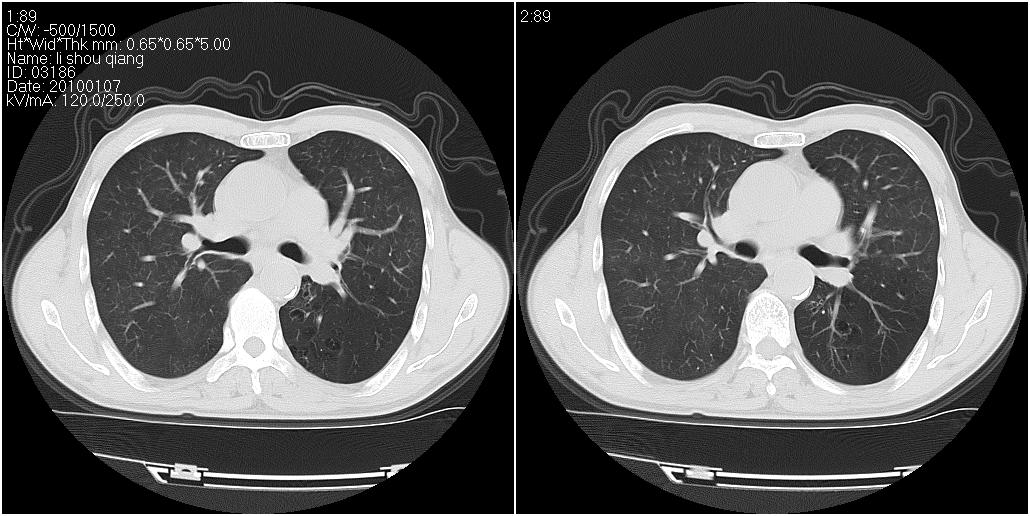

右肺中叶外侧段见一不规则的软组织肿块,边缘可见毛刺,并见厚壁空洞,与胸膜分界欠清。另左下肺见多个小囊状扩张区

右肺中叶外侧段可见团块影,外形不规则,内见空泡征。左下肺见蜂窝状低密度透亮影,部分层面主动脉旁瘤样突出。考虑右肺中叶外围型肺癌可能性大,左下肺支气管扩张,主动脉弓瘤样突出。